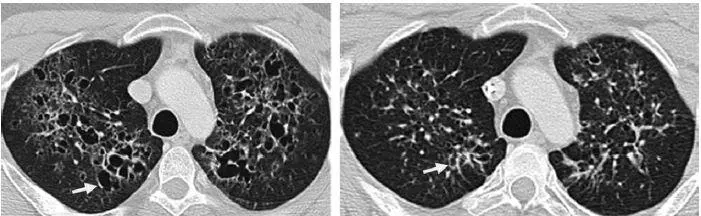

早期疾病薄层断层扫描(CT)可显示1–10mm的小叶中心结节或者空洞(图1)。随着病情的发展,囊性病变逐渐取代结节,表现为厚或薄壁囊腔,形态多不规则(图2)。结节和囊性病变通常累及双肺上中野,肺尖和肺底以及肋膈角常不受累。约25%的患者由于胸膜下囊腔破裂导致自发性气胸,累及双侧并且可以反复发作,这是本病的首发症状(图3)。终末期疾病的特点是肺过度充气以及广泛的囊腔,形成终末期肺气肿(图4)。薄层CT具有特征性人口统计学分布特点及临床表现,是PLCH临床诊断的重要依据,从而避免肺活检。在儿童中,薄层CT表现与成人相似,但更病变更广泛(图5),并且与未发现与吸烟有关的病灶。

图4 28岁男性PLCH患者。薄层CT横轴位(a)显示形态各异的囊变,全身性朗格汉斯细胞增多症化疗后两年随访显示囊变减小(b)